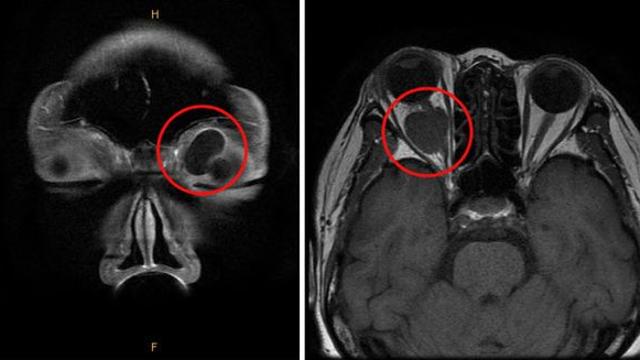

눈 주변에 생기는 종양, ‘안와 양성 종양’ 종류와 치료법은